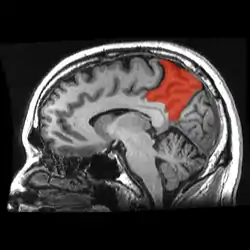

![]() Sagittal MRI slice with the precuneus shown in red. | |

Medial surface of left cerebral hemisphere. (Precuneus visible at top left.)